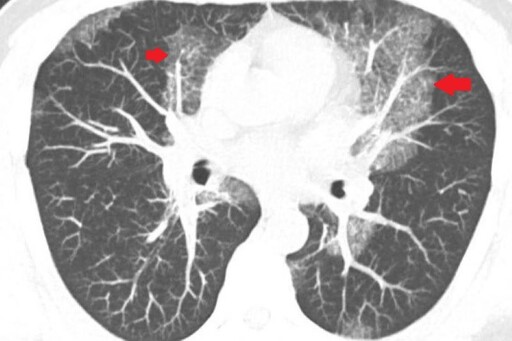

40歲的魏先生一向體格健壯,從事搬運工作多年,體能不輸年輕人。然而,近兩年來他逐漸感覺力不從心,肺活量明顯下降,時常出現間歇性暈眩,甚至有數次在搬運重物時,突然吸不到氣,胸口像是被重物壓住般喘不過氣來。近期他更在平時活動中出現背部劇烈疼痛,這才引起他的警覺,前往診所檢查,意外發現肺部有大片白影,隨即轉診至台北慈濟醫院胸腔內科。藍冑進主任與醫療團隊全面評估,電腦斷層初步研判為肺部慢性發炎,但進一步的支氣管鏡檢查卻顯示氣道清晰無異常,連同細菌與黴菌等各項培養檢查也均為陰性,病因成謎,只能密切追蹤病況,但三個月後卻發現雙肺白影惡化,最後,魏先生接受電腦斷層導引下的肺部穿刺切片,確診為極為罕見的肺部蛋白質沉積症(Pulmonary Alveolar Proteinosis, PAP)。

根據國外研究統計,蛋白質沉積症的發生率僅約百萬分之一。藍冑進主任指出:「目前醫學對該病的病因仍未完全明瞭,推測與自體免疫系統異常有關。正常情況下,肺部會分泌表面張力素等蛋白質,協助肺泡維持張開、促進氣體交換。但當這些蛋白質異常累積且無法被自然代謝清除,就會堵塞肺泡,進而導致缺氧、呼吸困難,嚴重時甚至可能危及生命。」此疾病在早期常無明顯症狀,容易與肺炎、肺纖維化等疾病混淆,導致誤診與治療延誤,因此提高臨床警覺性至關重要。